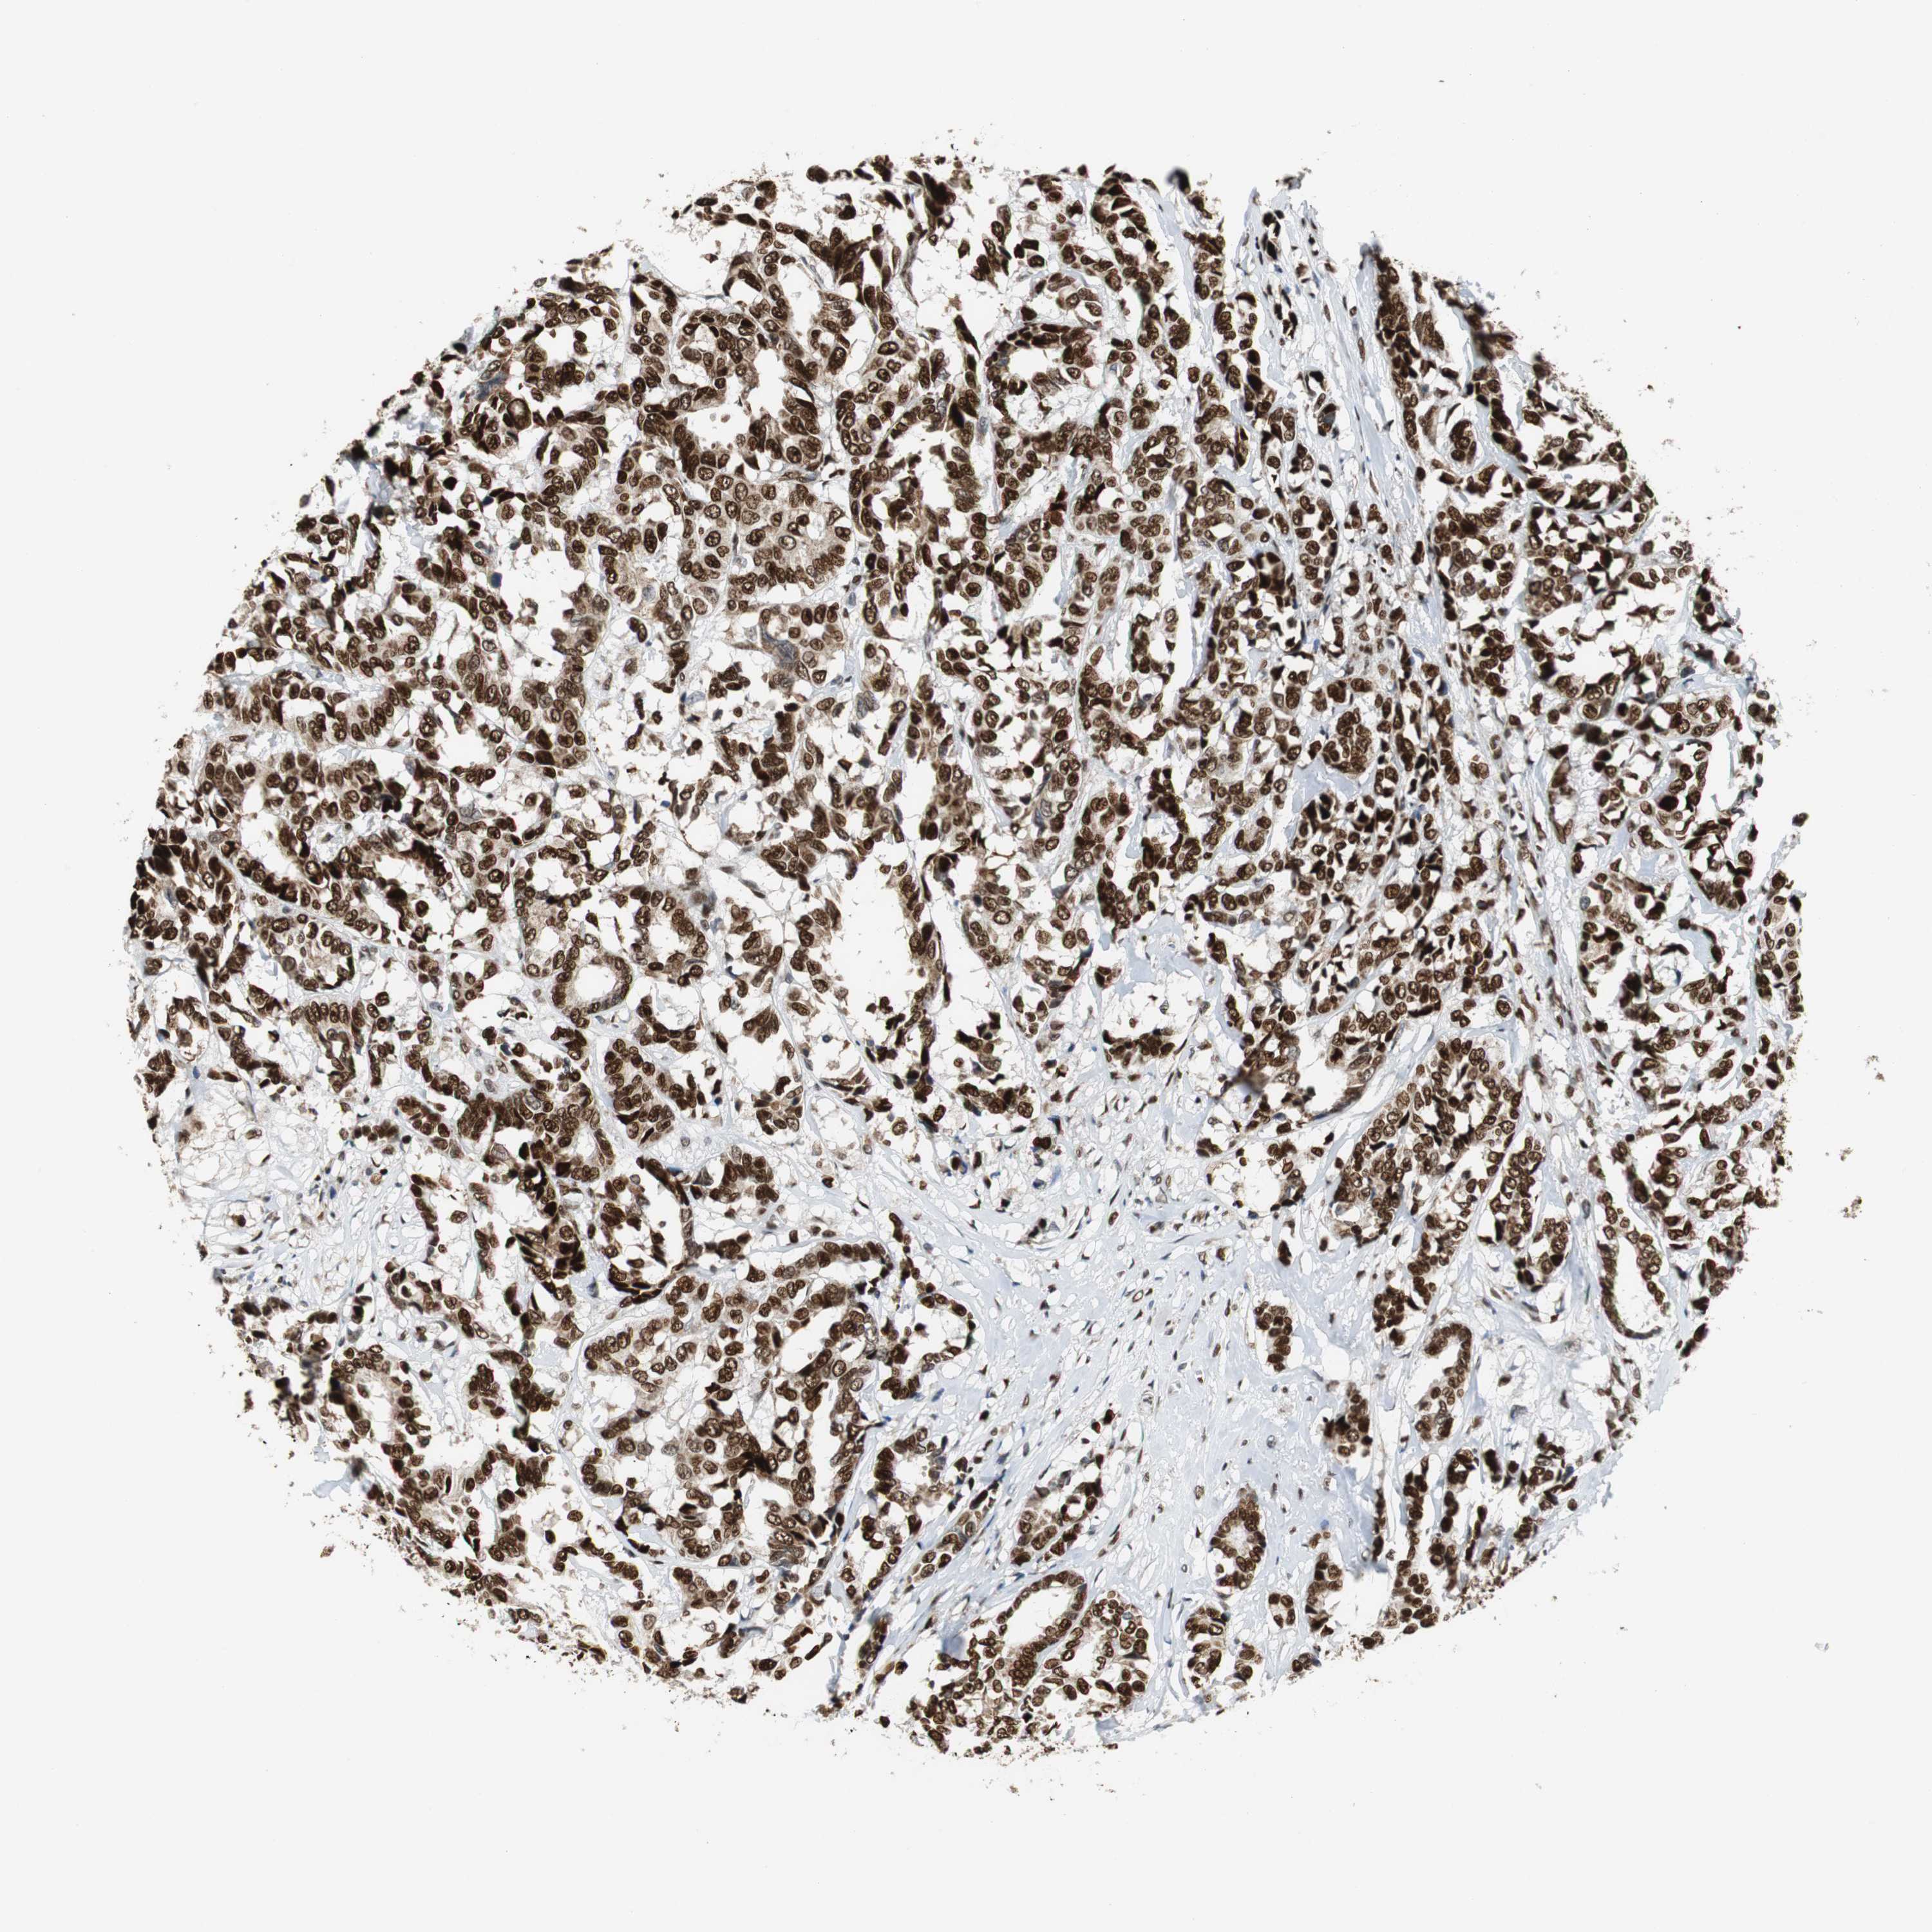

HDAC1

BRCA TCGA BRCA VALIDATION PROTEIN EXPRESSION